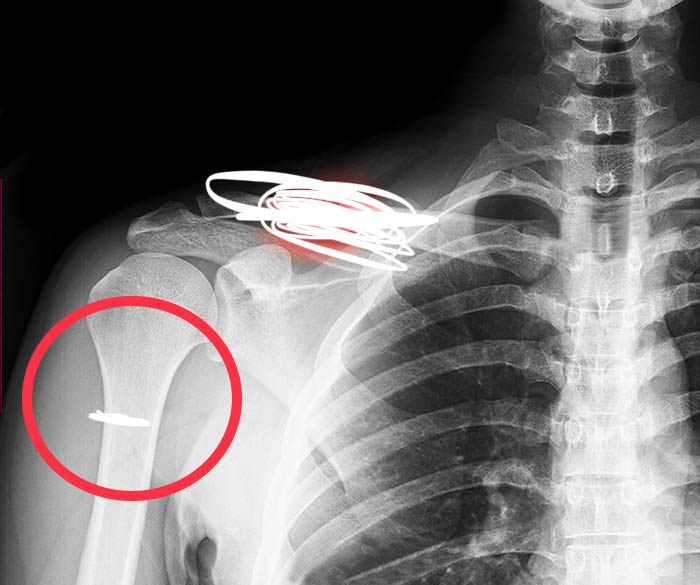

Сломал руку сын. Сказали 21-25 дней в гипсе. У меня паника, ну как так получилось, как я не уследила 😭 Вот в этом месте слопал, слава богу без смещения.

У кого так было, все ли хорошо и быстро срослось? На завтра назначили расслабление гипса и на 5 день рентген. Наложили в 1-й Детской. Вроде норм там хирурги? Или стоит сходить ещё к кому нибудь ?